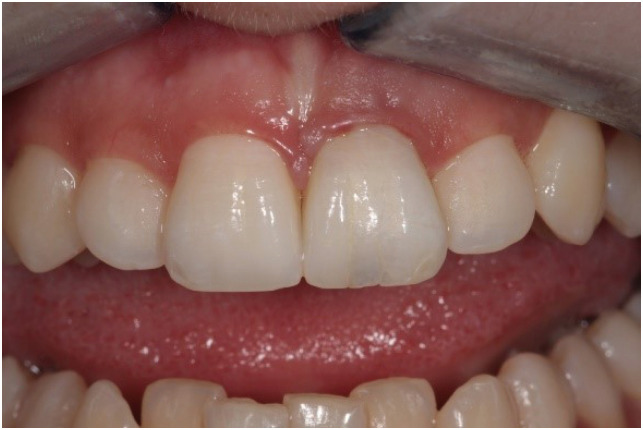

A 20-year-old woman with a history of root canal treatment of the upper maxillary (left) central incisor was referred to our department from a private clinic. The root canal treatment had been initiated 4 months prior but could not be finished. A clinical examination revealed a temporary filling on the palatal surface. The coronal part of the tooth was discolored, and multiple visible cracks were present on the buccal surface (Figure 1). The tooth was asymptomatic; the mobility was normal, and the probing depth at all sites was ≤ 3 mm. A periapical radiograph revealed a lesion around the apex and an enlarged and clearly irregular root canal (Figure 2A). When specifically asked, the patient denied knowledge of any previous dental trauma. Upon checking the electronic documentation of the faculty of the institution, we found that the patient had visited the department 2 years prior for other reasons, and X-rays were taken at that appointment. From a comparison of the periapical X-rays, it was clear that something must have happened since her last visit (Figure 2B). After gaining her confidence, the patient and her mother admitted that the patient had suffered from domestic abuse at the hands of her boyfriend, but that had been taken care of by the police. At this point, a small-field-of-view high-resolution cone-beam computed tomography (CBCT) scan was taken to investigate the extent and irregularity of the lesion. The scan confirmed the presence of a periapical lesion, which had destroyed most of the buccal bony wall around the root. The scan also showed massive internal resorption inside the root canal (Figure 2C). The patient was informed of the findings and the poor prognosis of the tooth, but since she desperately wanted to keep her tooth, she provided consent for endodontic treatment, which was initialized at a later appointment. The patient was also informed that due to the irregular nature and more pronounced buccolingual extent of the resorptive lesion and the massive destruction of the buccal bony plate, which cannot be seen or monitored on periapical X-rays, it would be beneficial to control the steps of the treatment and perform the monitoring via CBCT scans. The patient was informed of the extra radiation exposure resulting from the CBCT scans, but she insisted on undergoing scans instead of periapical X-rays when deemed beneficial by the clinicians.

Figure 2

Images of the patient's tooth upon presentation and 2 years prior. (A) X-ray image upon presentation. (B) X-ray of the same tooth from 2 years prior. (C) Cone-beam computed tomography image of the tooth upon presentation.